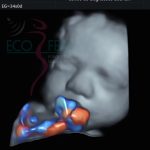

Imágenes de ultrasonido

Contamos con equipo médico con tecnología de punta y lo más importante: ¡Médicos altamente capacitados para entregarte mejores diagnósticos!